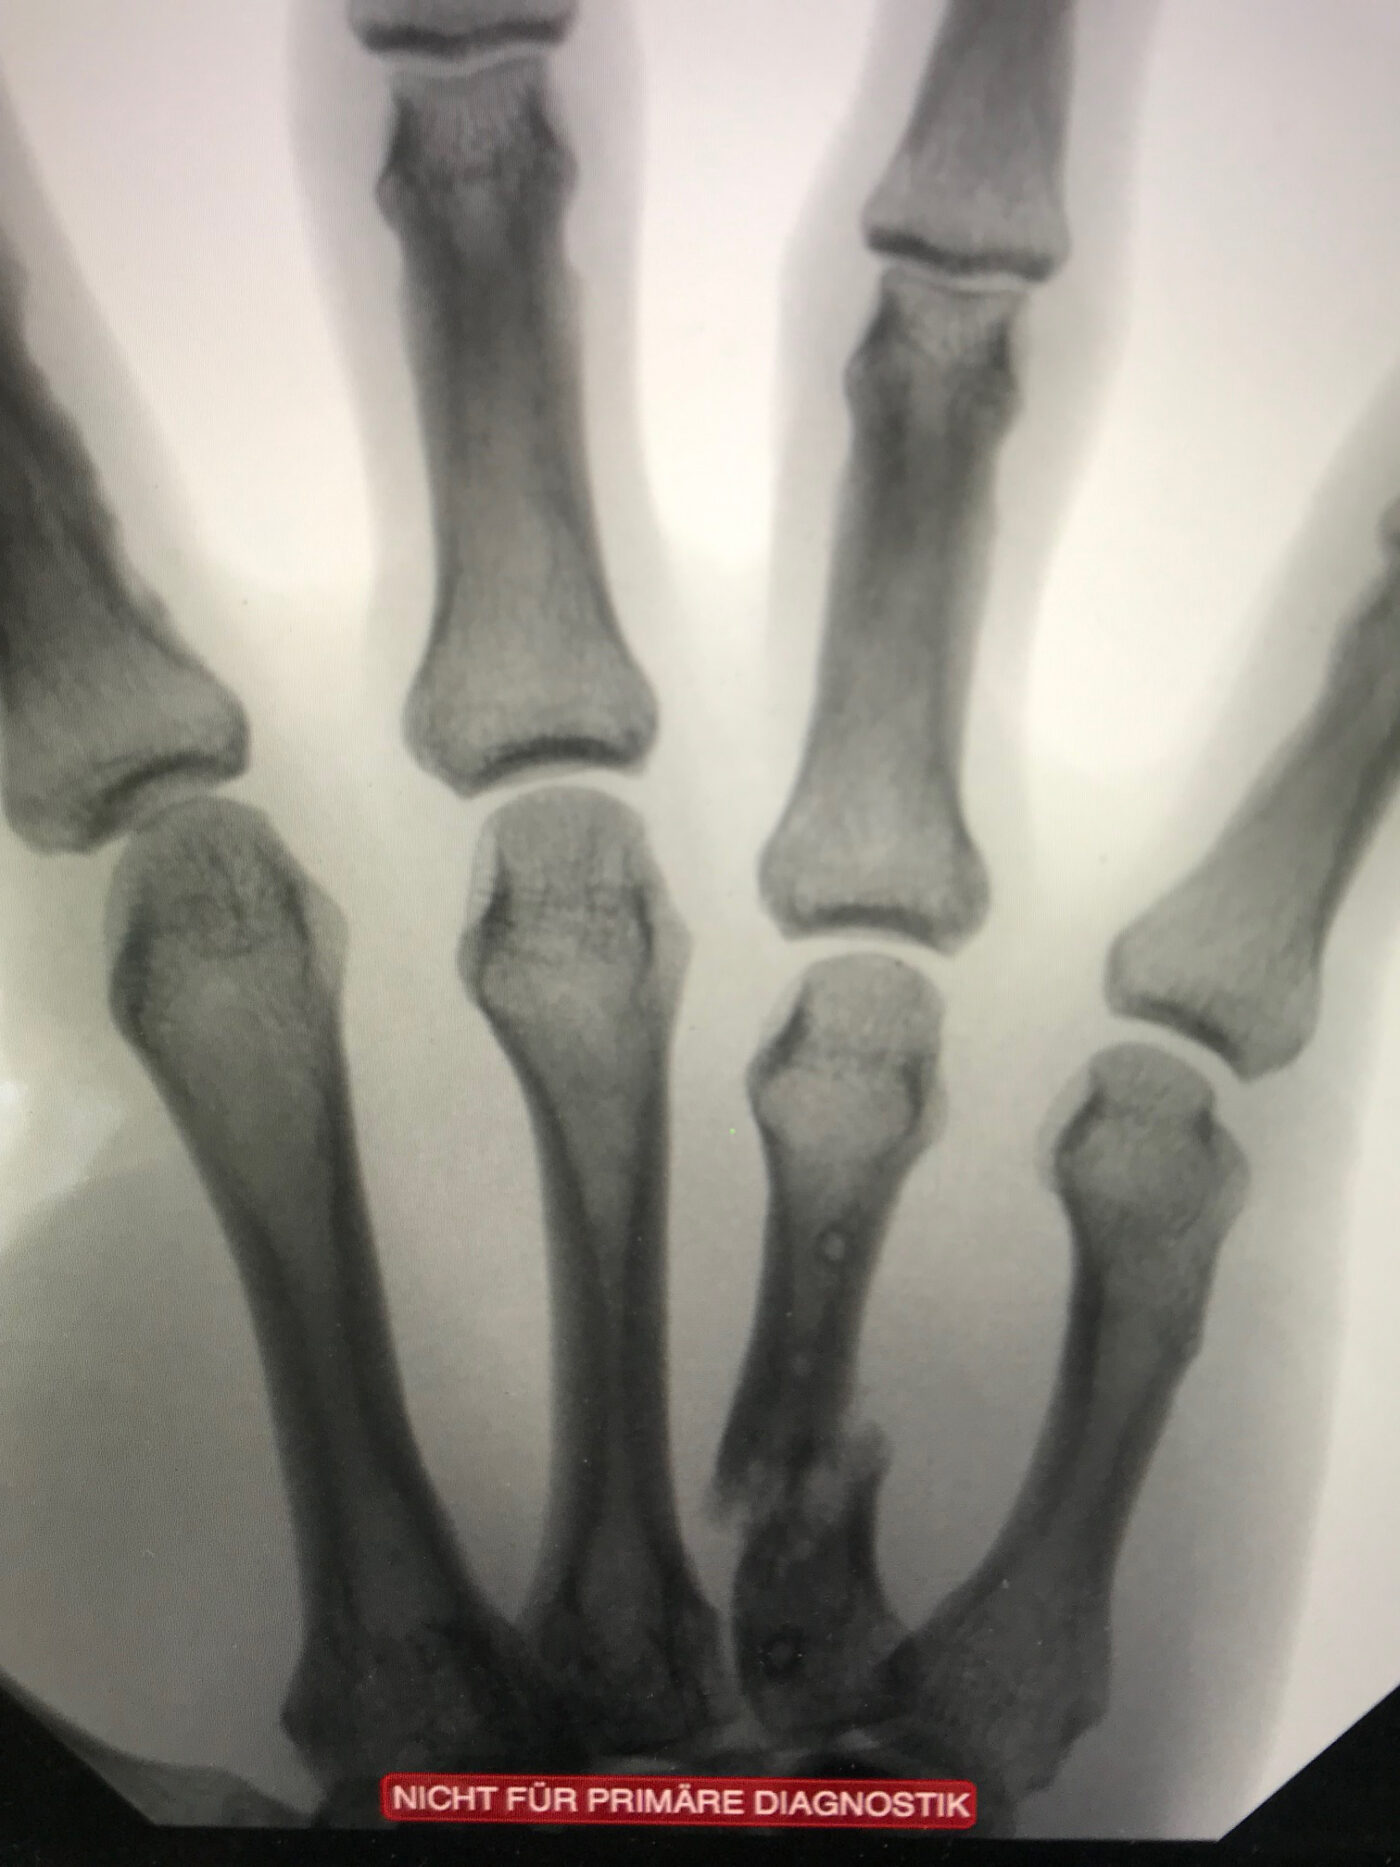

Der Kanadier erlitt zum vierten Mal einen Knochenbruch in seiner rechten Hand: Nach Zeigefinger- und kompliziertem Daumenbruch hielt ein weiterer Finger der enormen Wucht des Pucks nicht stand. «Aus ärztlicher Perspektive hätte man die Operation sofort durchführen müssen. Durch das Warten wurden die Finger immer krummer und kürzer», erinnert sich Dr. Jürgensen.

Doch solche Bedenken und Schmerzen halten Eishockeyspieler nicht vom Eis fern: Ein bisschen «Tape» muss reichen. Mit den Worten «As long as you win», liess der Handchirurg den Spieler wohl oder übel gewähren. Erst eine Woche nachdem der SCB den Sieg geholt hatte und die Siegesfeiern vorbei waren, wurde endlich operiert. In einer aufwändigen Rekonstruktion entnahm Dr. Kay Jürgensen Knochen von der Speiche und transplantierte diese an den Mittelknochen – wo vorher ein Loch war. «Den Finger habe ich wieder auf die richtige Länge gebracht und richtig eingestellt».